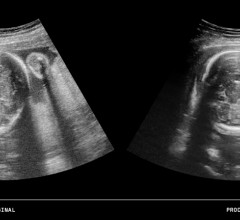

September 17, 2014 — The industry’s first ultrasound real-time 3-D volume enhancement product from ContextVision has been paired with brand new image visualization capabilities. The resulting product, REALiCE, will deliver photo-realistic and improved diagnostic-quality 3-D ultrasound images.